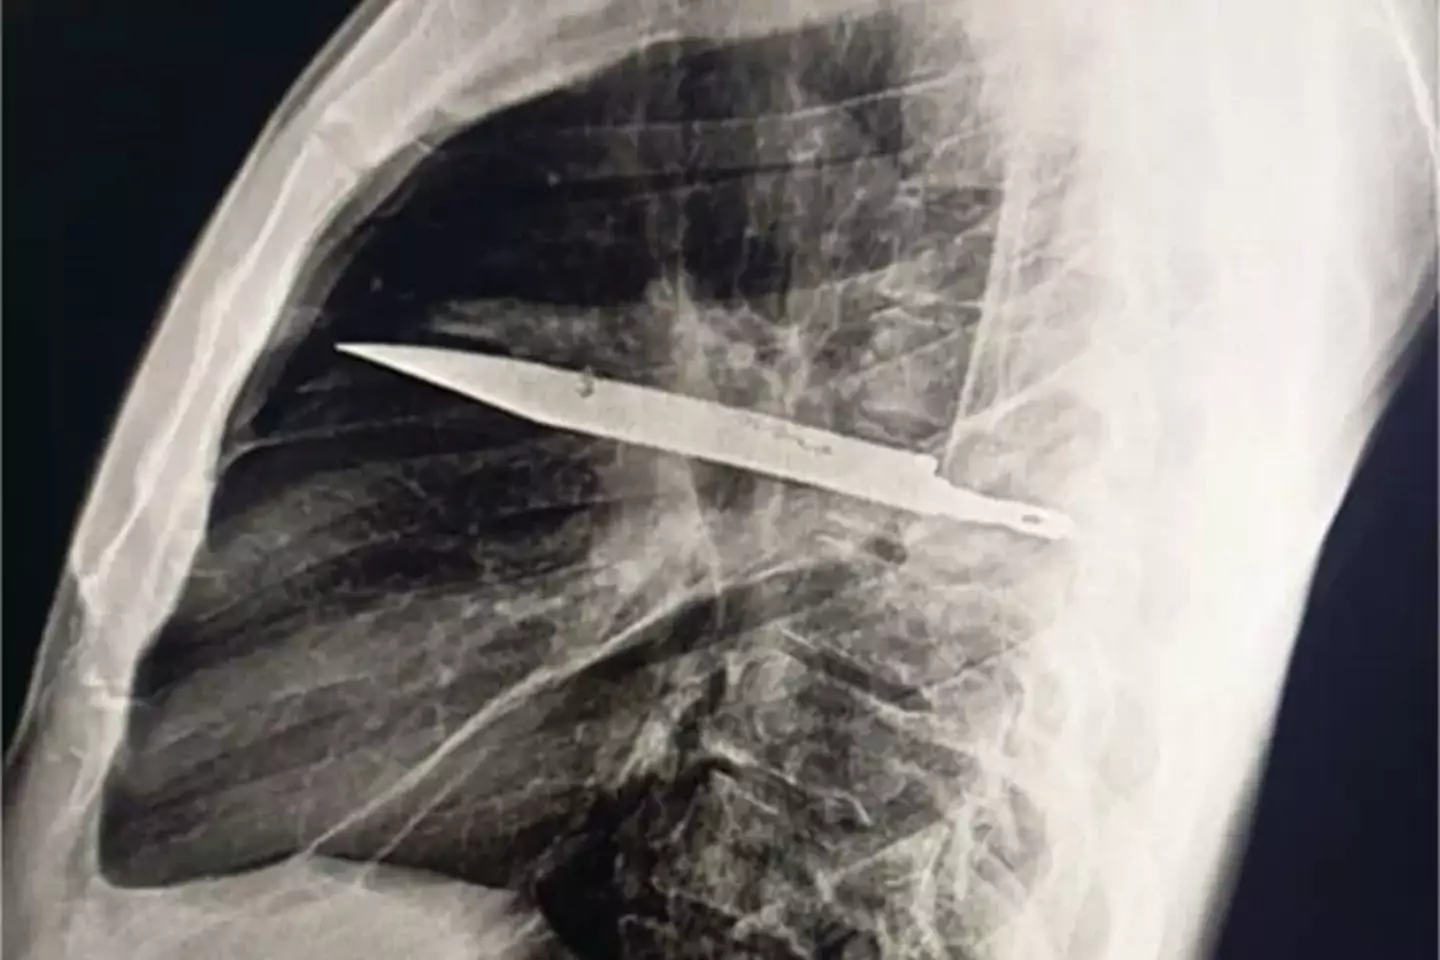

Sometimes truth is stranger than fiction, after an X-ray revealed the man had a sizeable knife buried deep inside his chest.

After ordering an X-ray, a 'retained metallic object' was found, and medics realised it was a knife, and it was surrounded by 'pus and necrotic tissue'.

It had entered his body through his right shoulder.